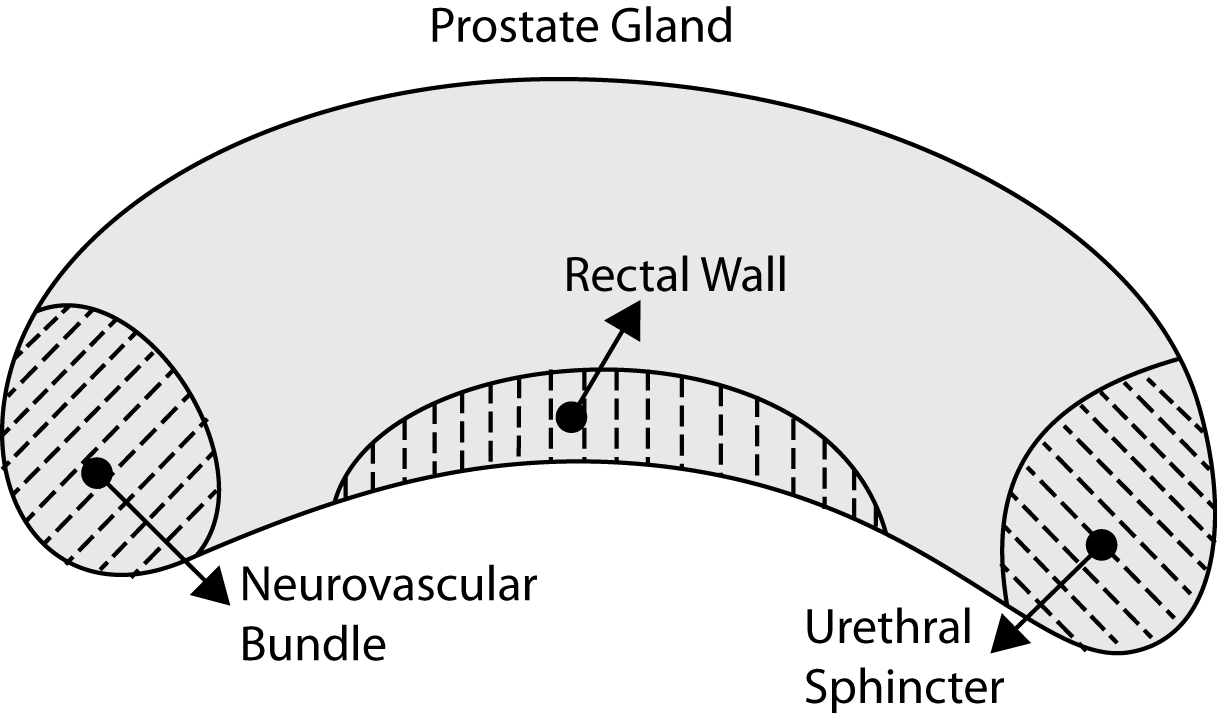

One can show that and , hence . It is obvious that can come from an algorithm in which case is the ground-truth from one or multiple users. As well, can be manual delineation by an expert whereas is then gold standard as consensus among multiple experts. For instance, when segmenting the prostate gland, one has to actually pay more attention to some specific zones such as the rectal wall, neurovascular bundle and urethral sphincter (Figure 2, left). In many cases, a segment may have a large overlap with the ground-truth but may not be accurate enough in significant zones (Fig. 2, right). The accuracy of such segments should be penalized according to the zonal accuracy.